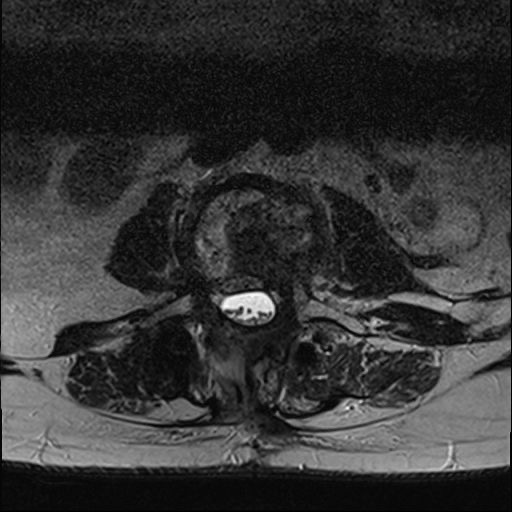

Chory został przekazany do Oddziału Neurochirurgii Szpitala Kopernika w Łodzi, gdzie w wykonanym badaniu MRI kręgosłupa stwierdzono guza trzonu L3, ze złamaniem patologicznym tego trzonu i naciekiem kanału kręgowego z krytycznym jego zwężeniem (stopień 3 wg ESCC).

Implanty kompozytowe z włókna węglowego są przezierne dla promieniowania jonizującego, przez co nie generują artefaktów w badaniach pooperacyjnych, co pozwala na doskonałą jakość obrazowania i dalszej obserwacji radiologicznej (Zdjęcie 6 i 7).